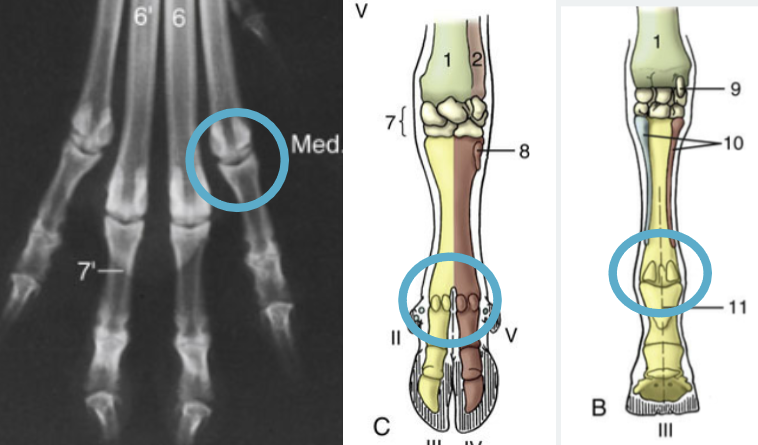

Which joint it shown?

Metacarpophalangeal Joint

Green arrow?

Proximal interphalangeal joint

Red arrow?

Distal interphalangeal Joint

Tarsus

14

If on the hind limb, what joint?

Metatarsophalangeal